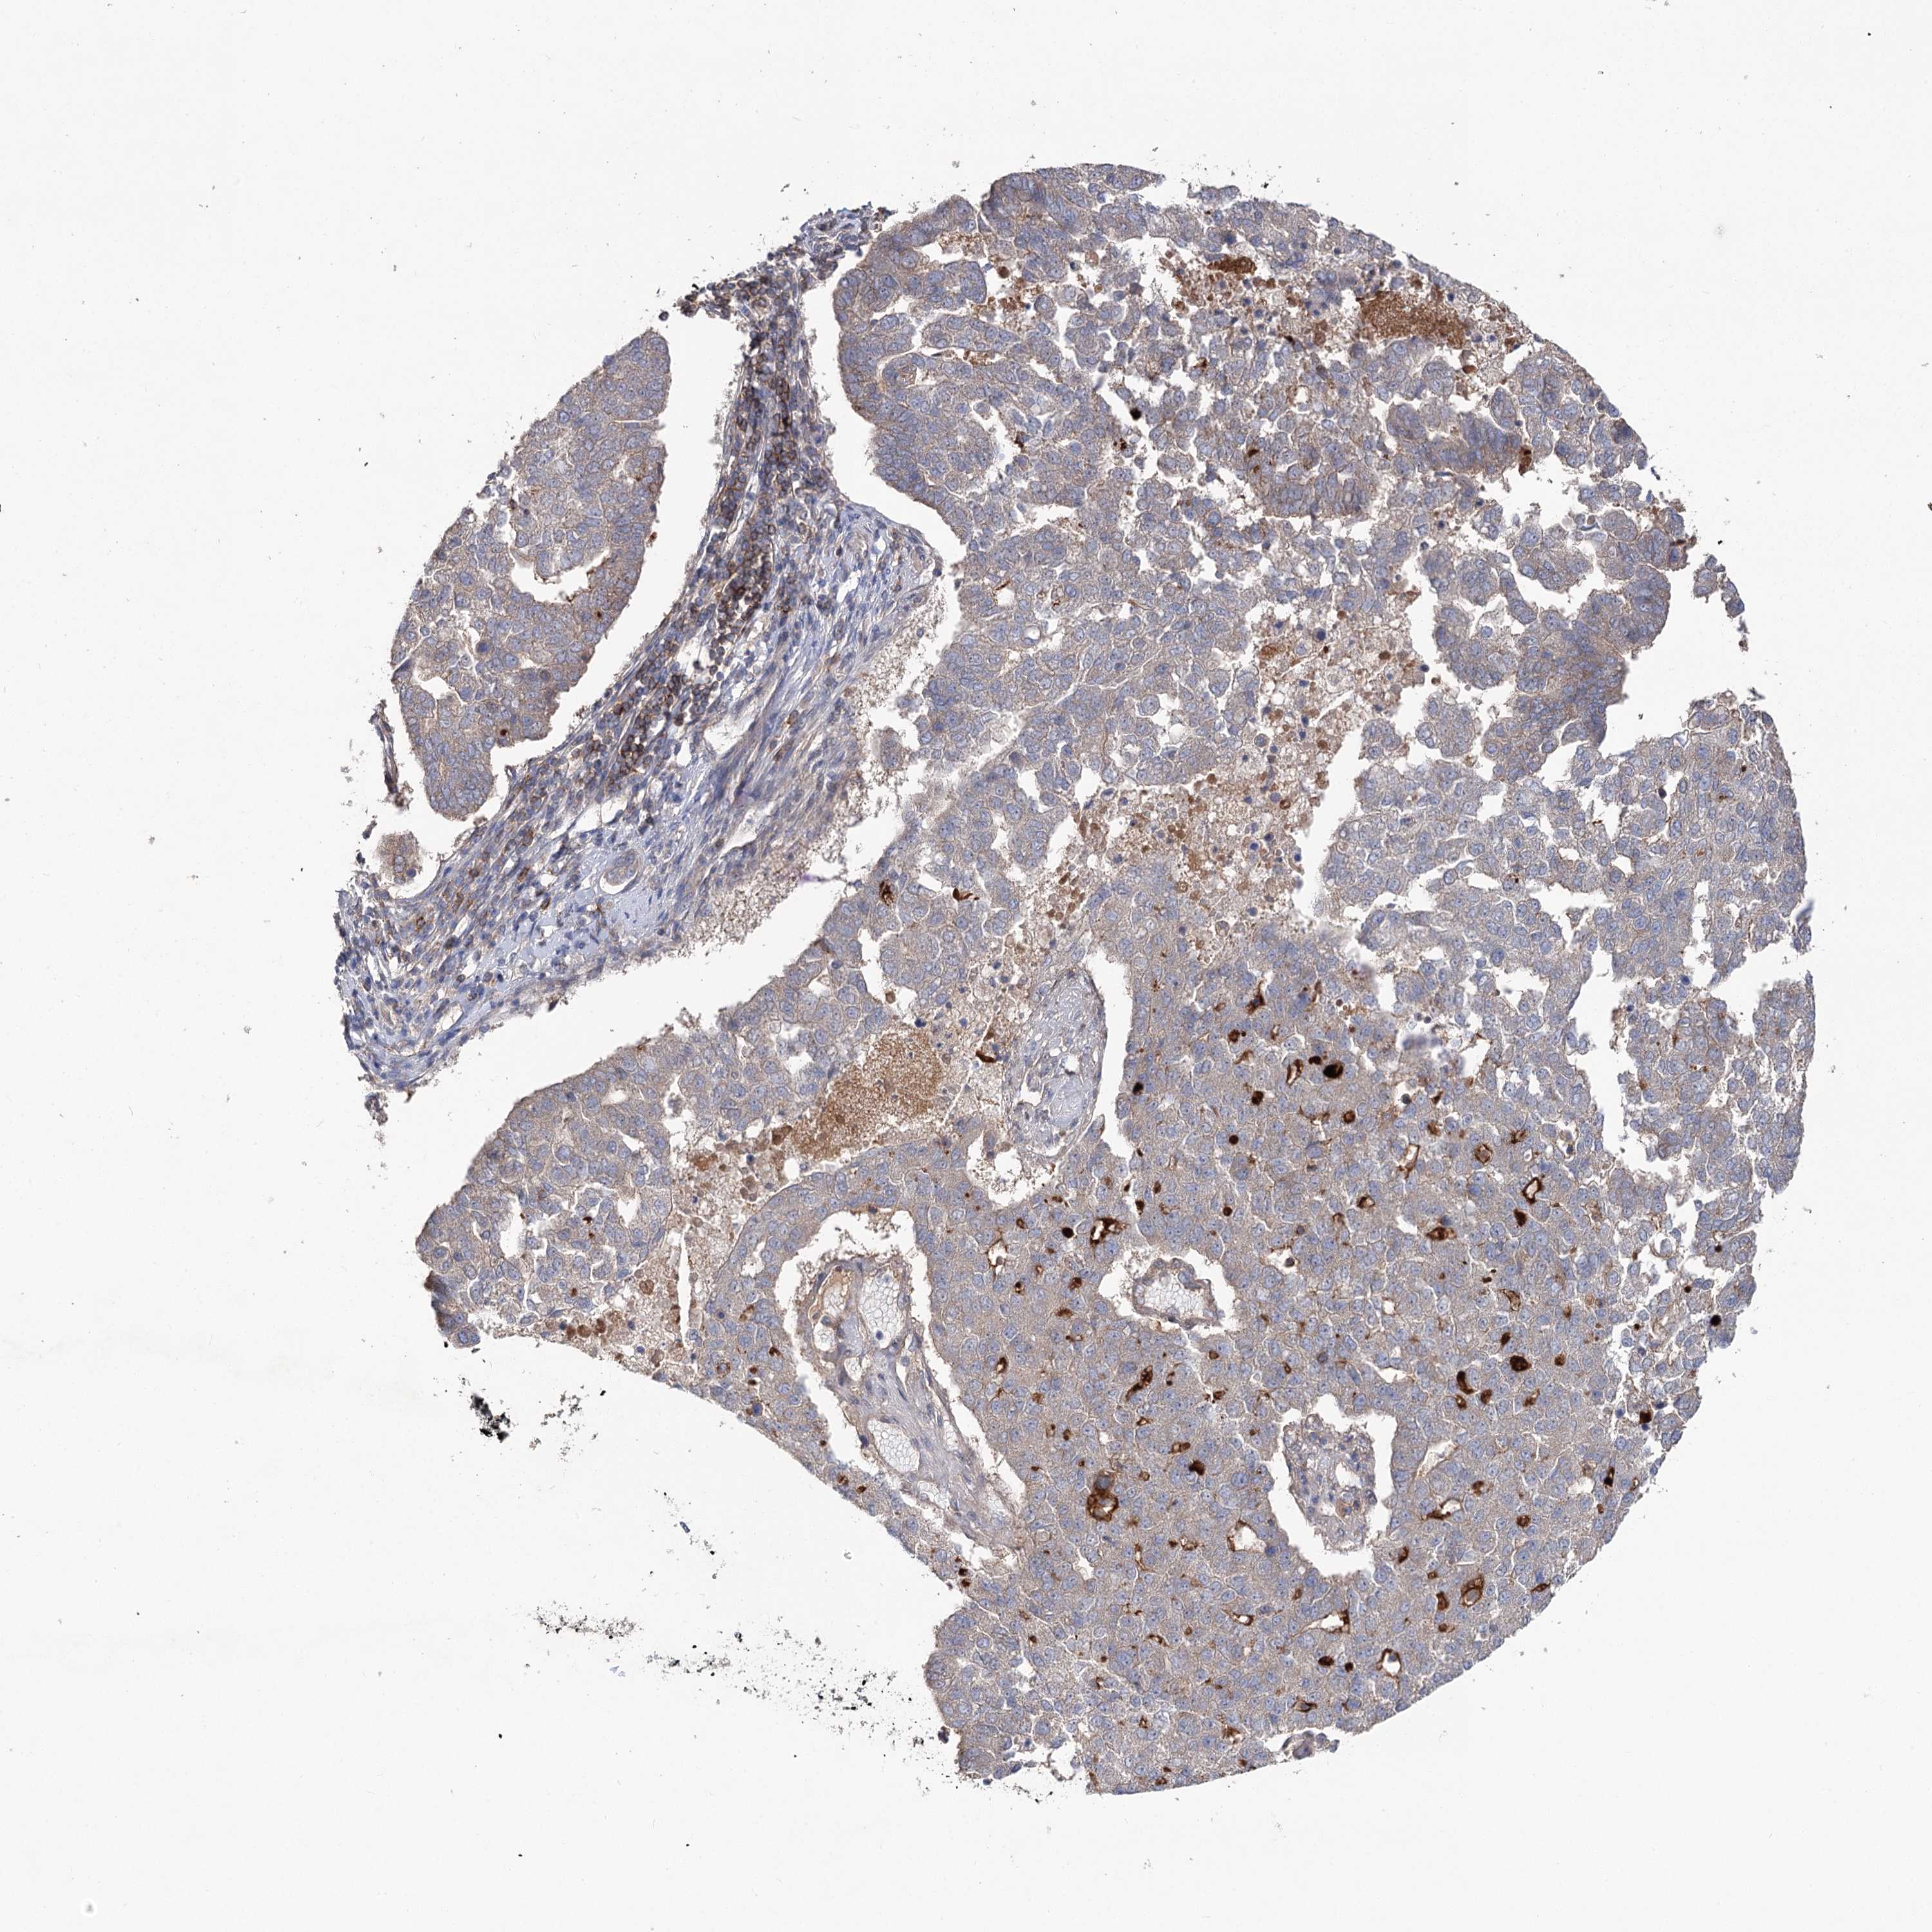

PANCREATIC CANCER - Protein expressioni

A mouse-over function shows sample information and annotation data. Click on an image to view it in a full screen mode. Samples can be filtered based on level of antibody staining by selecting one or several of the following categories: high, medium, low and not detected. The assay and annotation is described here.

Note that samples used for immunohistochemistry by the Human Protein Atlas do not correspond to samples in the TCGA dataset.

Antibody stainingi

Antibody staining in the annotated cell types in the current human tissue is reported as not detected, low, medium, or high, based on conventional immunohistochemistry profiling in selected tissues. This score is based on the combination of the staining intensity and fraction of stained cells.

Each image is clickable and will lead to virtual microscopy that enables deeper exploration of all samples and also displays staining intensity scores, fraction scores and subcellular localization as well as patient and tissue information for each sample.

Antibody HPA038557

Antibody HPA038558

Staining

High

Medium

Low

Not detected

Intensity

Strong

Moderate

Weak

Negative

Quantity

>75%

75%-25%

<25%

None

Location

Nuclear

Cytoplasmic/membranous

Cytoplasmic/membranous,nuclear

Adenocarcinoma, NOS